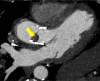

Cardiovascular imaging has significantly evolved since the turn of the century. Progress in the last two decades has been marked by advances in every modality used to image the heart, including echocardiography, cardiac magnetic resonance, cardiac CT and nuclear cardiology. There has also been a dramatic increase in hybrid and fusion modalities that leverage the unique capabilities of two imaging techniques simultaneously, as well as the incorporation of artificial intelligence and machine learning into the clinical workflow. These advances in non-invasive cardiac imaging have guided patient management and improved clinical outcomes. The technological developments of the past 20 years have also given rise to new imaging subspecialities and increased the demand for dedicated cardiac imagers who are cross-trained in multiple modalities. This state-of-the-art review summarizes the evolution of multimodality cardiac imaging in the 21st century and highlights opportunities for future innovation.